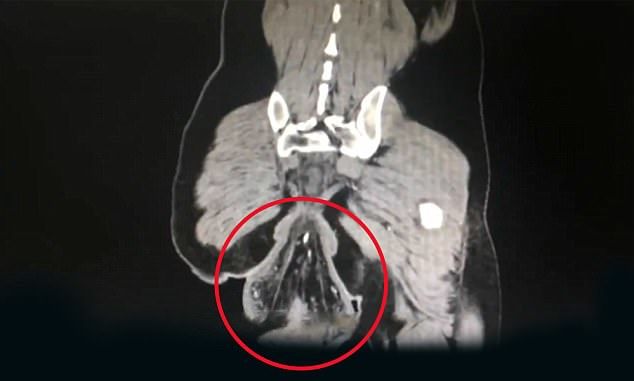

Une fois arrivé à l’hôpital, les médecins ont constaté que leur patient avait perdu le lien qui maintient le rectum bien en place dans le corps humain.

Les plus anxieux sont sans doute déjà au bord de l'évanouissement. Mais qu'ils se rassurent ! Ce Chinois souffrait depuis l'enfance d'un prolapsus rectal (ou relâchement du rectum).